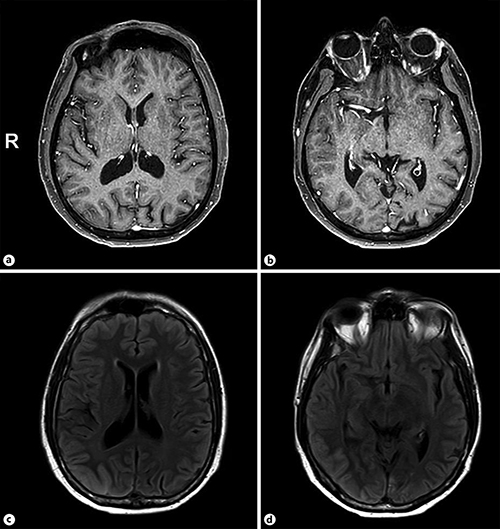

A Case of Hypertrophic Pachymeningitis Associated with Immunoglobulin Case Reports In Neurology Karger Articles from case reports in neurology are provided here courtesy of karger publishers. We report a very rare case of isolated accessory nerve palsy due to a large thrombosed aneurysm of the intracranial vertebral artery. Scilit source title profile of case reports in neurology scilit is a comprehensive content aggregator platform for scholarly publications. Published by karger online issn:. Case. Case Reports In Neurology Karger.

From karger.com